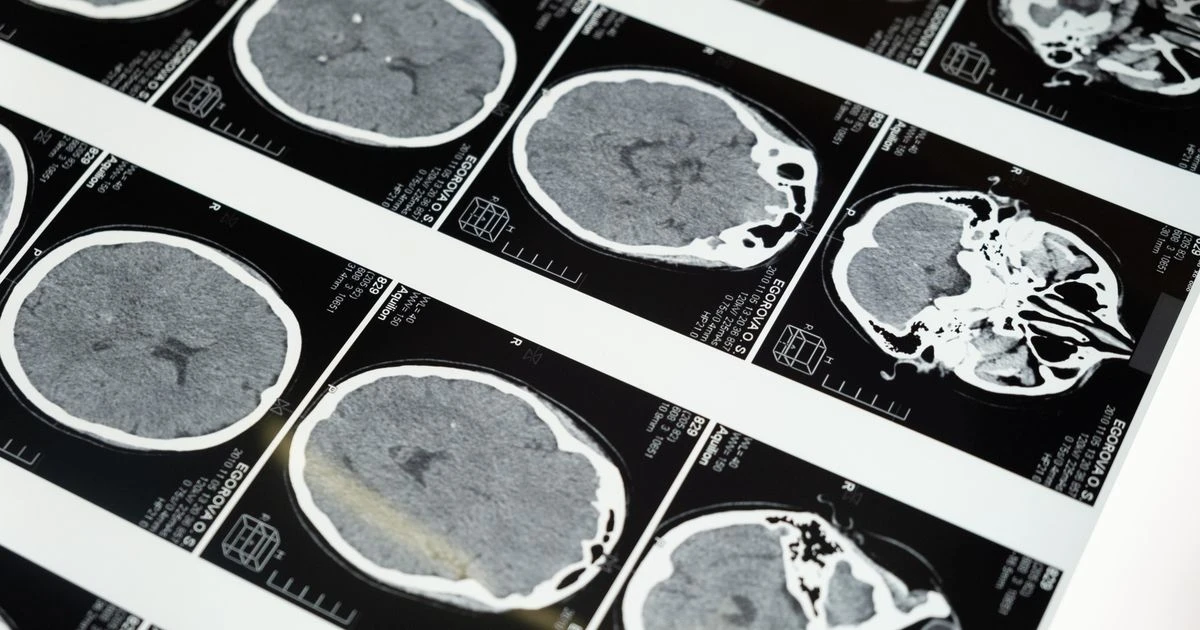

Dementia is usually associated with old age. However, some forms of dementia can strike astonishingly early and move frighteningly fast